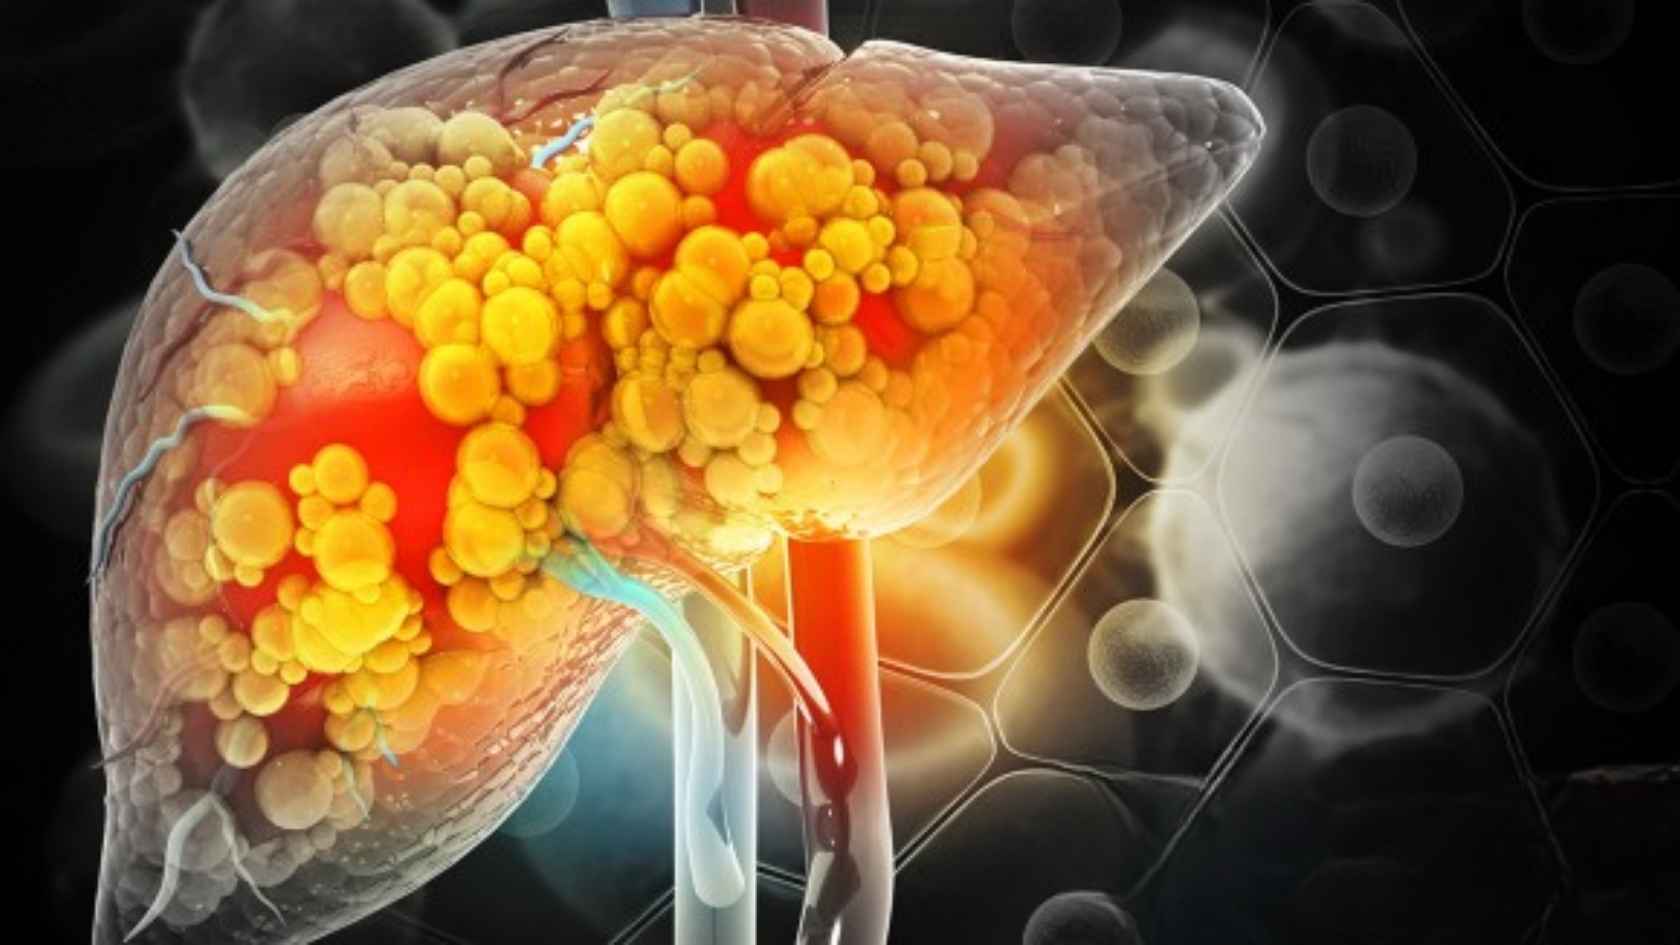

Type 2 diabetes damages your body from within. It weakens insulin response, disrupts blood sugar control, harms organs, and creates a metabolic imbalance. Standard treatment manages glucose but ignores the metabolic stress damaging your pancreas, liver, nerves, and vessels.